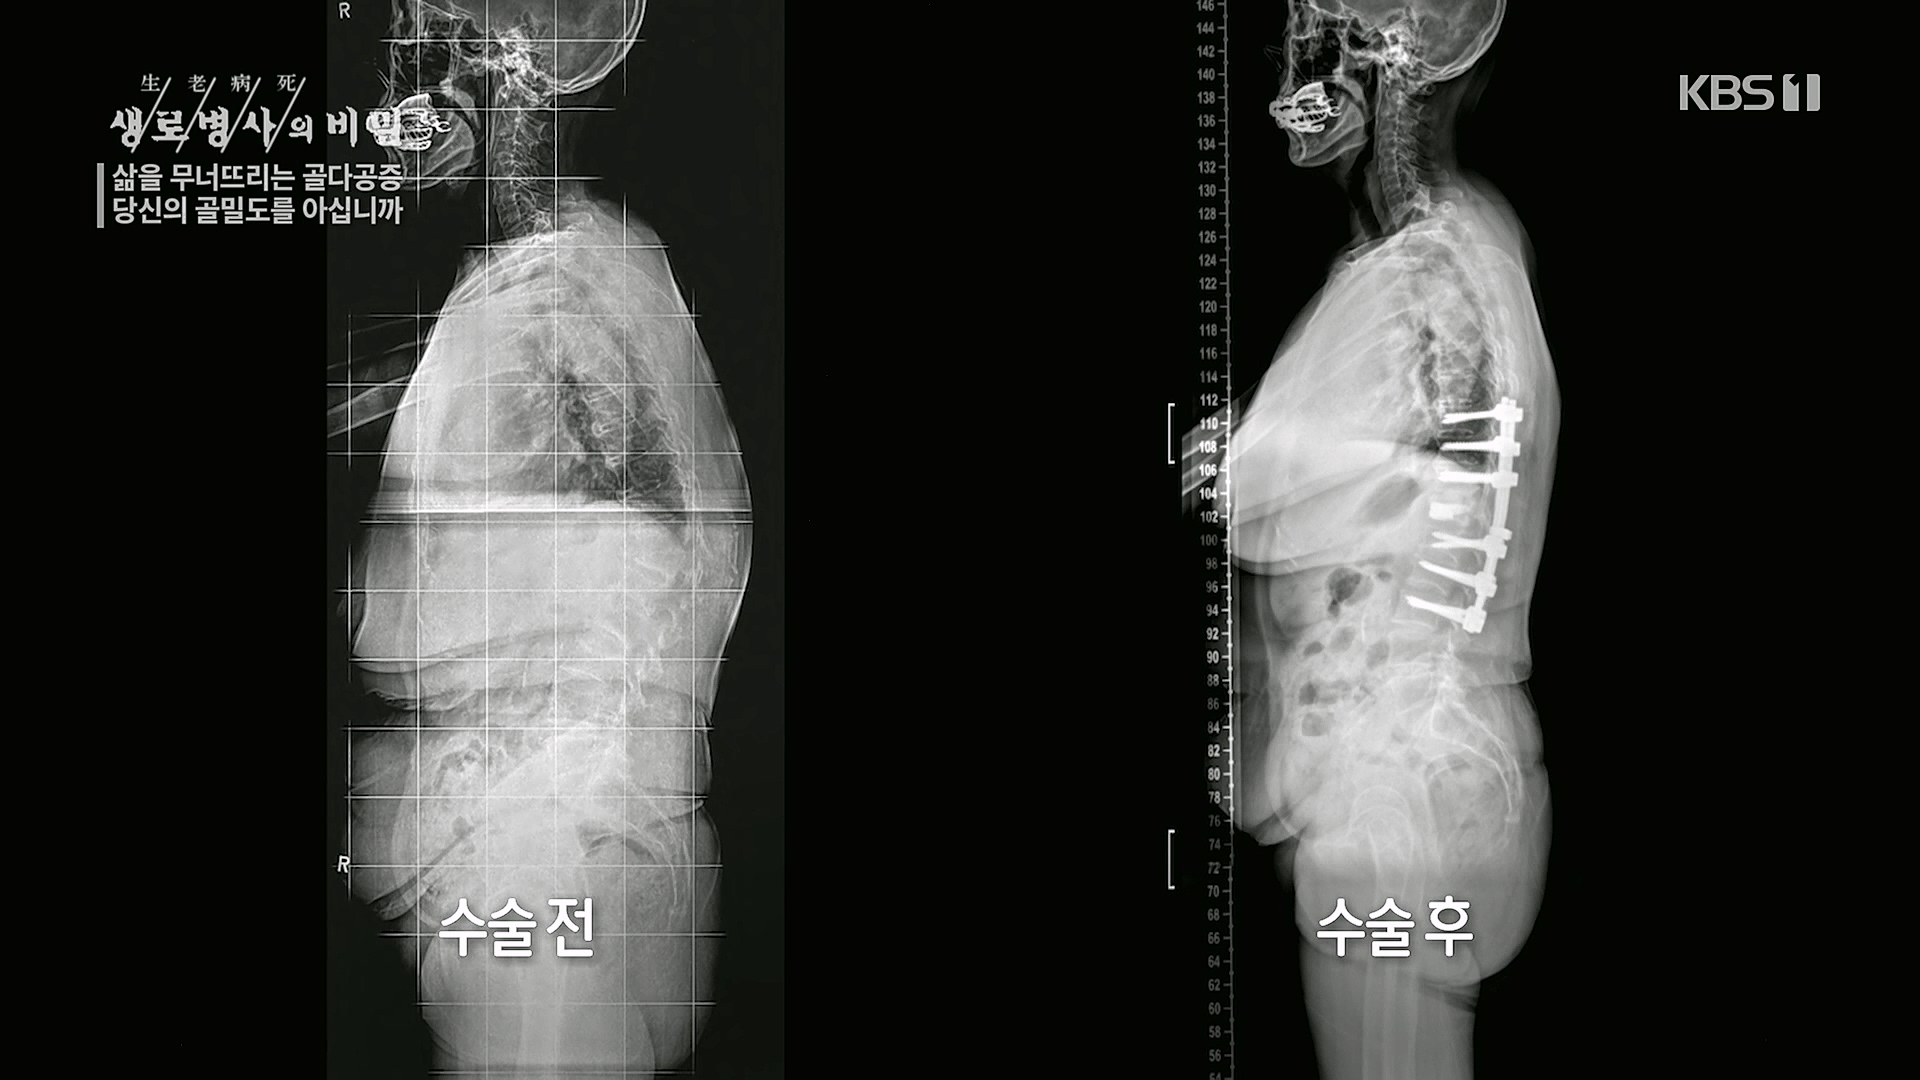

삶을 무너뜨리는 골다공증

당신의 골밀도를 아십니까